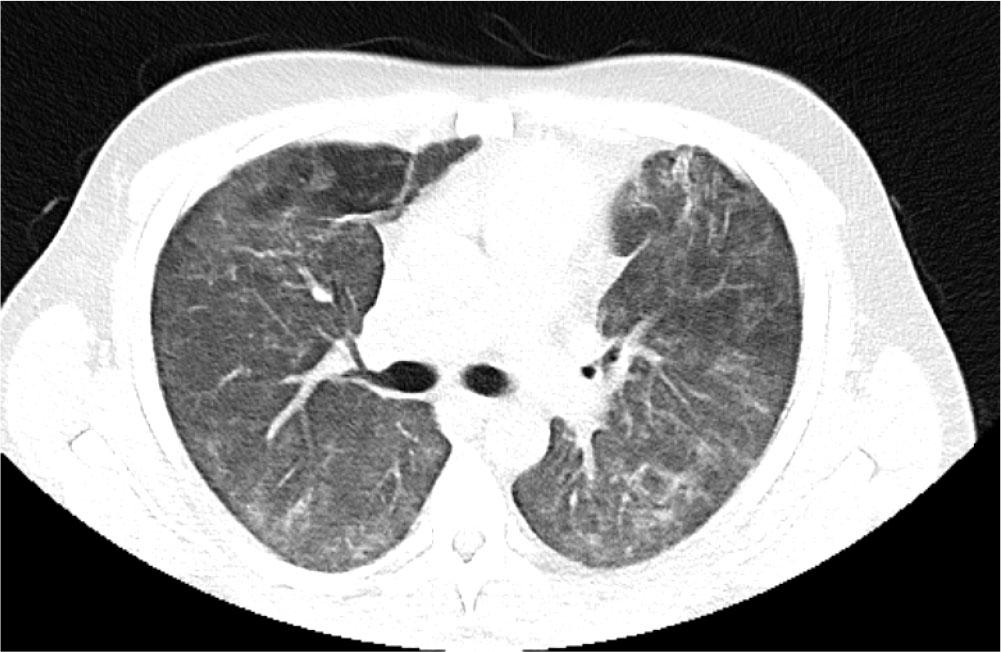

He was transferred to the ward for rehabilitation on day 68. A CT-thorax performed on Day 97 showed further improvement of bilateral infiltrates. There was residual ground glass opacification and reticular shadowing with minor traction bronchiectasis. These changes were consistent with interstitial fibrosis (Figure 4) and he was discharged home on 3L ambulatory oxygen, after 109 days. His hospital stay was complicated by reactivation of Cytomegalovirus and hospital acquired-pseudomonas pneumonia for which he was treated accordingly. He continues to have close follow-up with Rheumatology, Respiratory teams and attends the Critical Care follow up clinic. Currently he is weaning off the corticosteroid therapy and receives rituximab infusions every six months with mycophenolate mofetil 1g twice daily. Most recent CT Thorax performed 2 years post initial presentation showed resolution of bilateral infiltrates, however, upper lobe predominant reticulations and traction bronchiectasis were evident in keeping with interstitial fibrosis (Figure 5).

CT Thorax performed Day 92 prior to discharge home showing further improvement of both ground glass opacification and reticular shadowing with minor traction bronchiectasis.